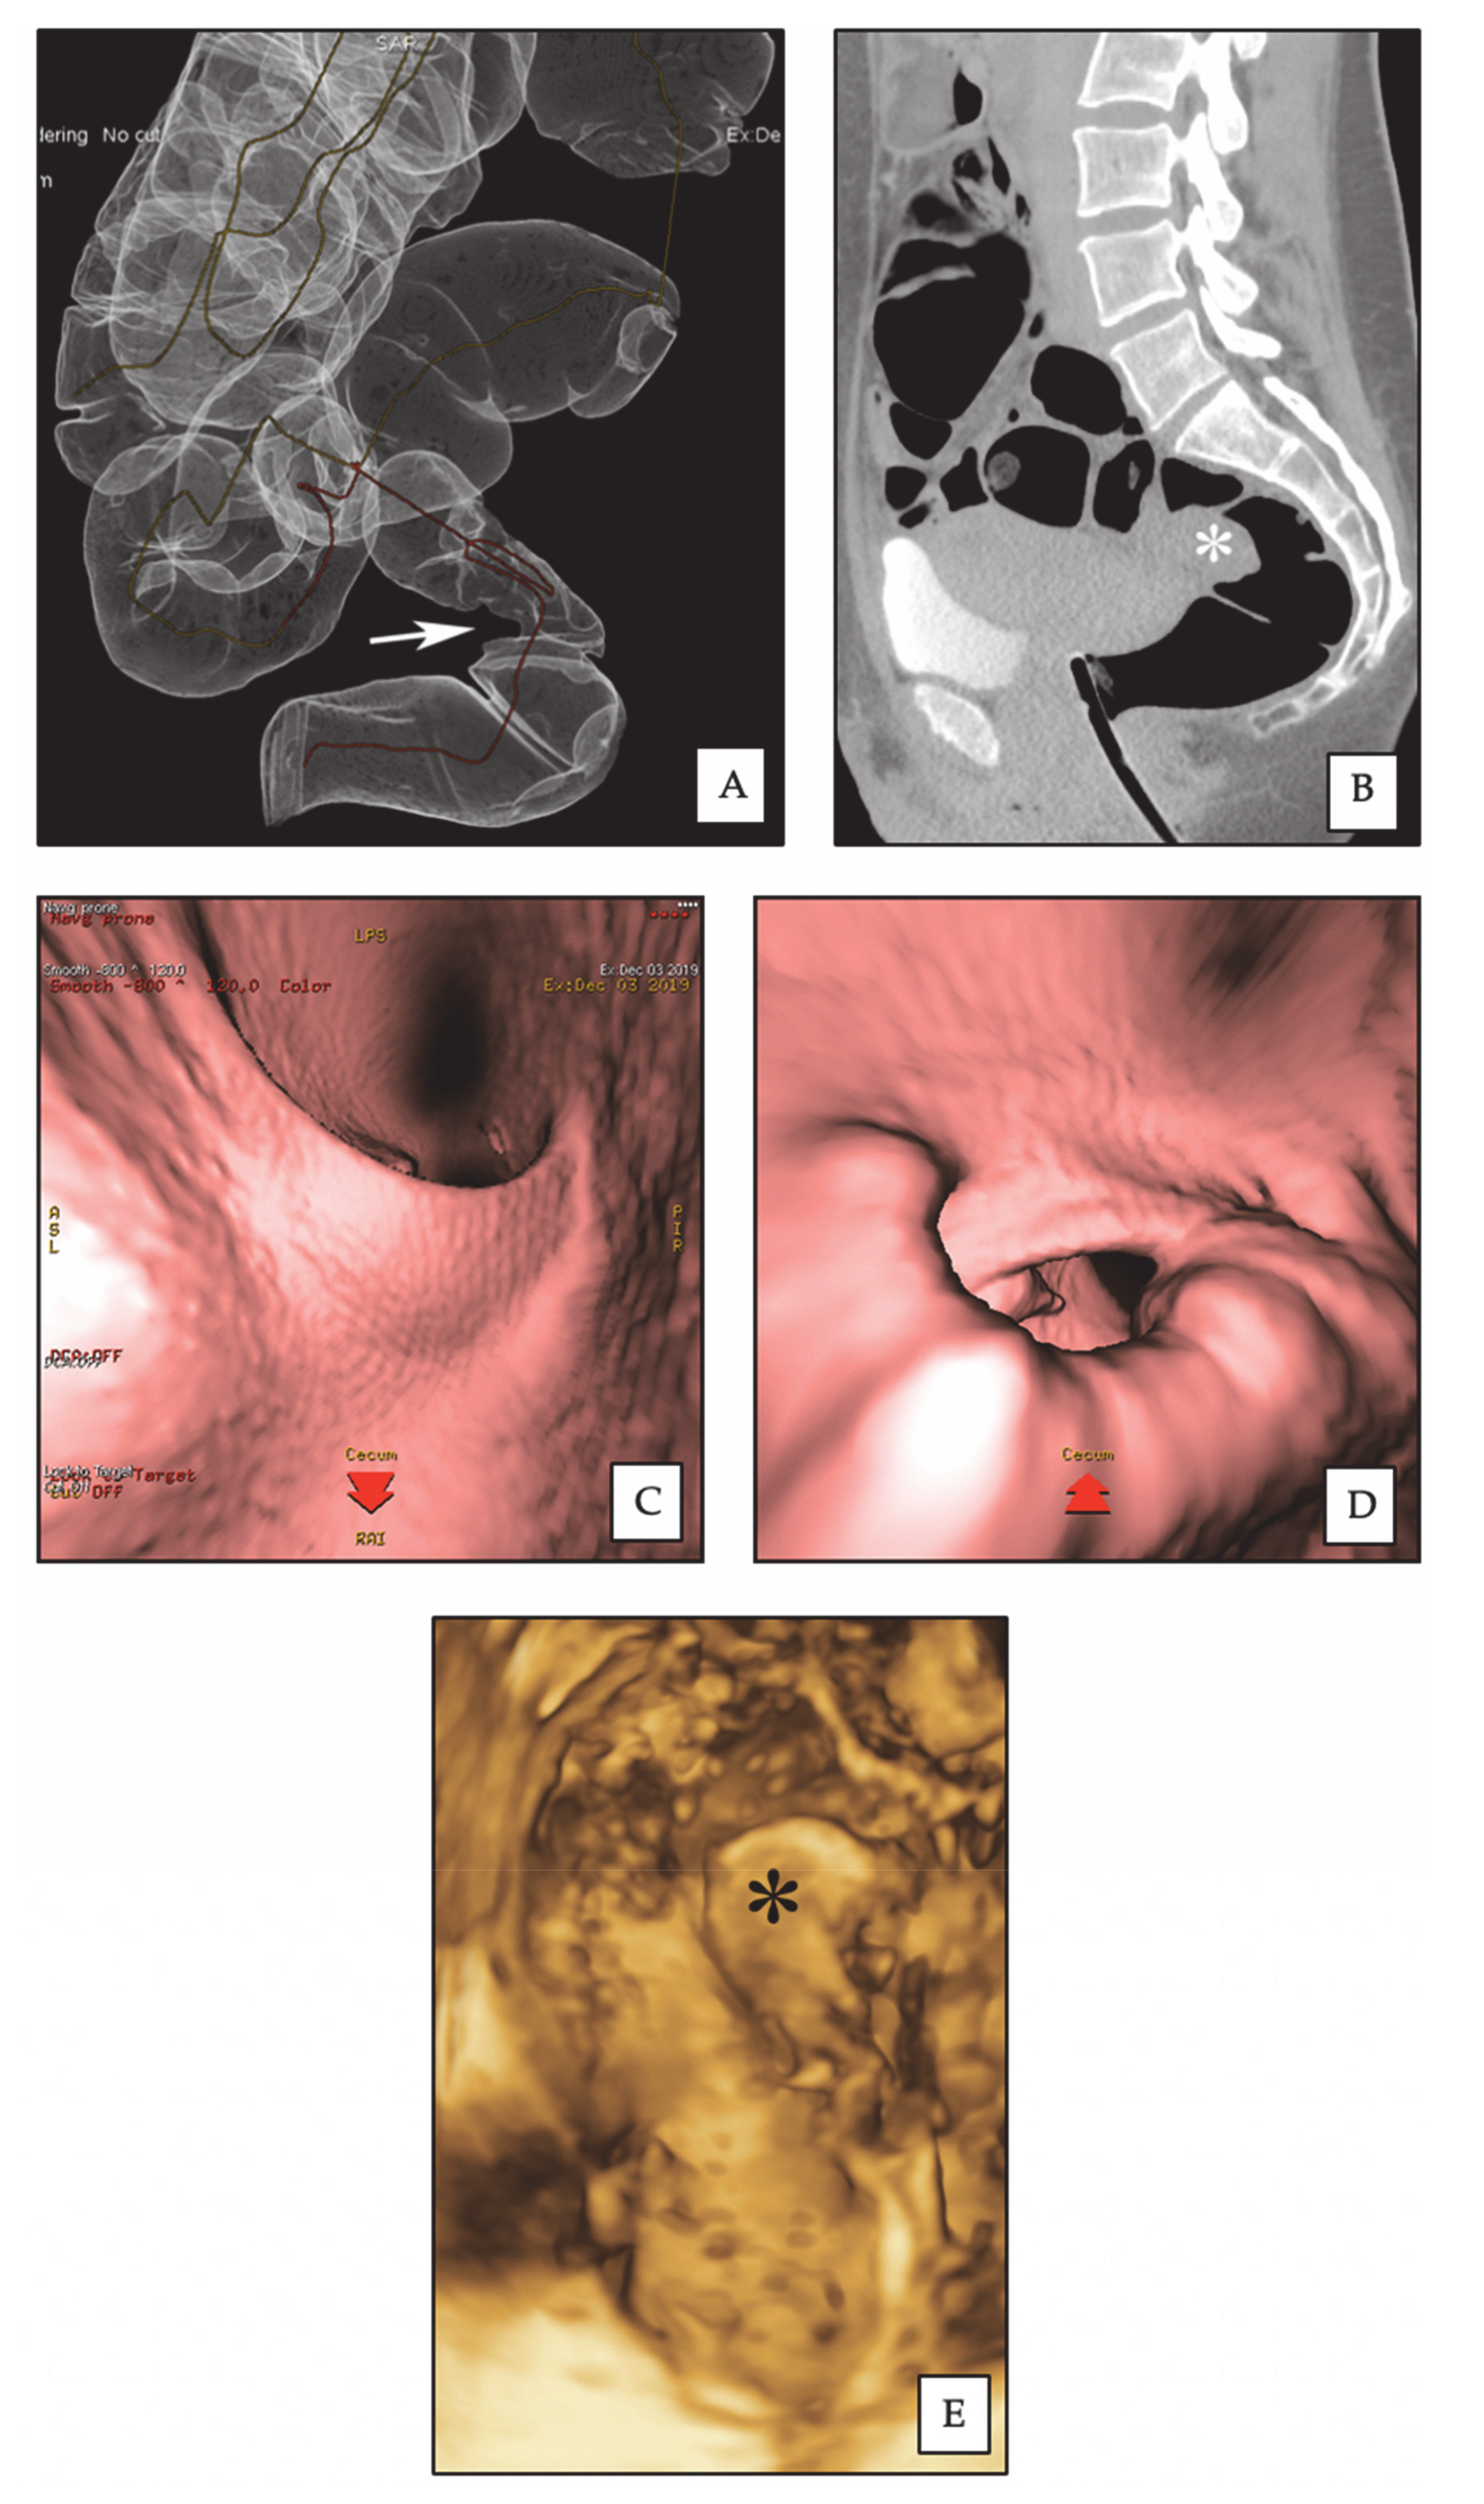

Rectosigmoid endometriotic nodules appear on CTC as strictures usually involving a variable part of the circumference of the bowel wall (Figure 1); the site of these findings is constant on both the supine and prone scans and stenosis may be highlighted by the 3D endo-luminal FT reconstructions (Figure 2). The MPRs sometimes allow for the detection of a transmural involvement of the endometriotic nodule [27].

Figure 2.

Rectal endometriotic nodule. (A) CTC: 3D reconstruction of dilated colon, showing rectal stenosis (arrow) by an endometriotic nodule. (B) CTC: sagittal 2D image, the rectal nodule (asterisk) causes stenosis of the intestinal lumen. (C) CTC: pseudoendoscopic view and 3D endoluminal fly-through reconstruction, showing normal rectal lumen. (D) CTC: pseudoendoscopic view and 3D endoluminal fly-through reconstruction, showing rectal stenosis by the endometriotic nodule. (E) 3D-RWC-TVS showing the rectal nodule (asterisk). The nodule has a largest diameter of 2.8 cm; the distance between the lower margin of the nodule and the anal verge is 10 cm.

3.2. Diagnostic Performance of 3D-RTW-TVS and CTC

3D-RTW-TVS and CTC detected 26 (70.3%) and 35 (94.6%) rectosigmoid endometriotic nodules out of 37 confirmed during surgery (Figure 2 and Table 2). There was no significant difference in the accuracy of 3D-RWC-TVS and CTC in diagnosing the presence of rectosigmoid endometriotic nodules (p = 0.118). However, a subgroup analysis demonstrated that CTC was more precise than 3D-RWC-TVS in diagnosing endometriosis located in the sigmoid (p = 0.016). In fact, 3D-RWC-TVS did not identify the presence of eight sigmoid nodules, whereas CTC did not identify only one sigmoid endometriotic nodule. The presence of an endometrioma with diameter >4 cm was positively statistically correlated to the lack of identification of sigmoid endometriotic nodules (phi coefficient 0.516; p = 0.039) during 3D-RWC-TVS, but not during CTC (phi coefficient 0.333; p = 0.182).